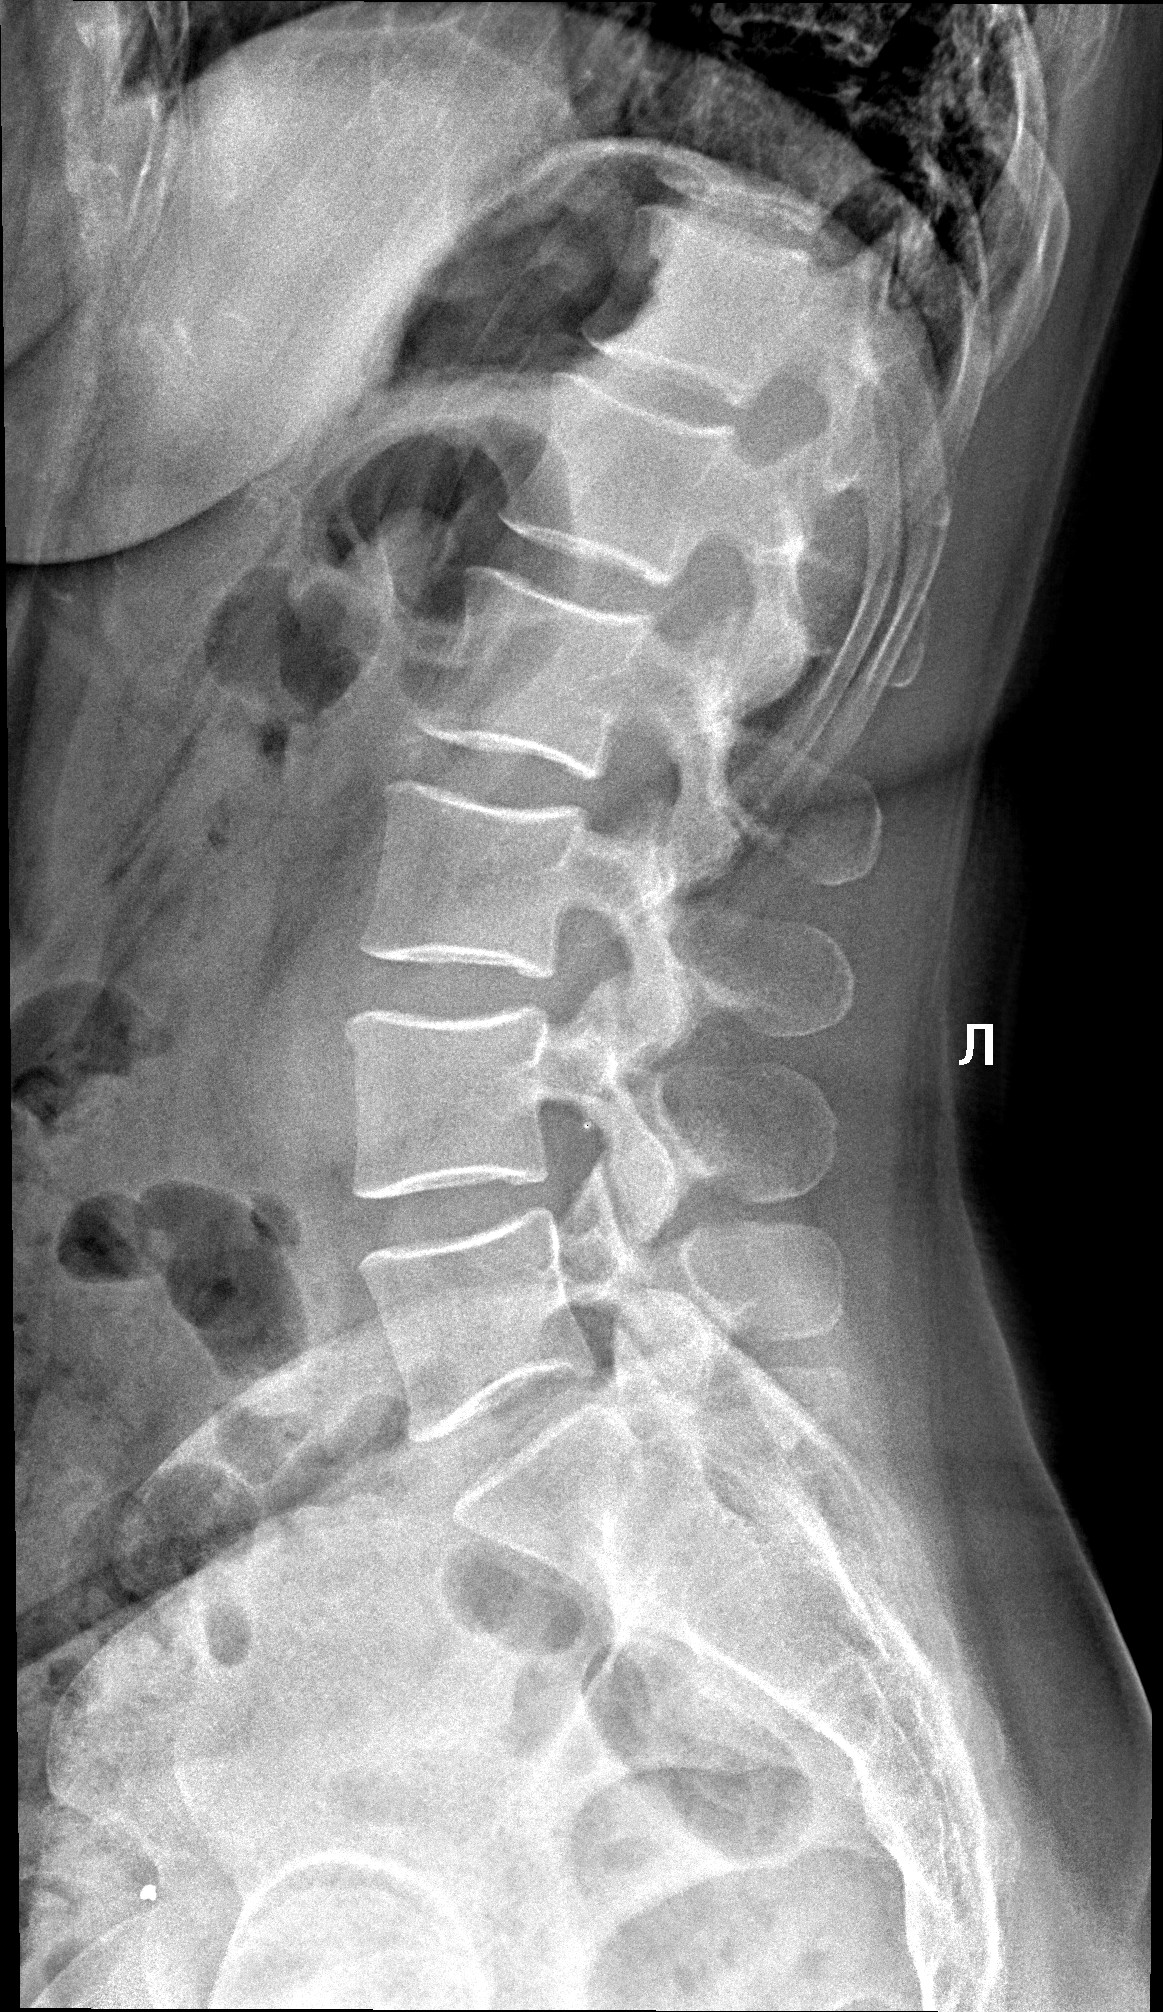

Медицинские снимки: рентген позвоночника сбоку